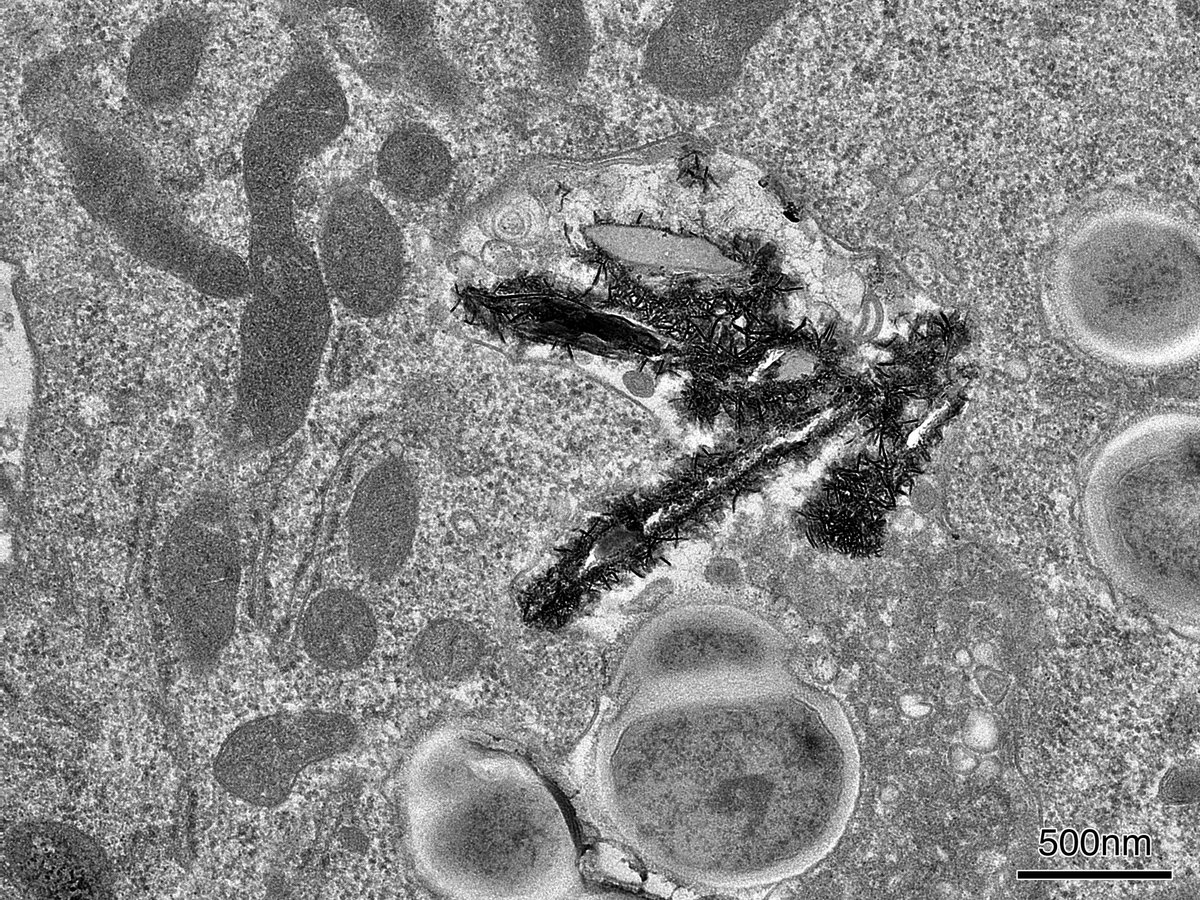

Thank you Nobu and Maria for this beaut image of a

#macrophage trying to deal with the#brakedust that it’s taken up. Note the airway#pathogens to the right- these guys are still growing in there!https://twitter.com/MRC_TU/status/1219652191461552128 …

A new study from researchers including our own

@DrLizaSelley found that brake dust - tiny metal particles released when a car brakes - may damage the immune system, preventing cells called macrophages from engulfing bacteria and clearing them awayhttps://www.telegraph.co.uk/science/2020/01/09/do-have-london-throat-scrapping-speed-bumps-could-help/ …Hvala. Twitter će to iskoristiti za poboljšanje vaše vremenske crte. PoništiPoništi -